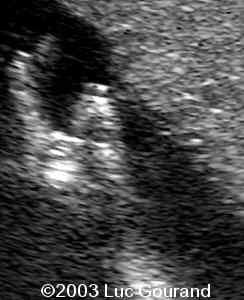

The following images were obtained in from second trimester fetus. The head demonstrated a cloverleaf skull, frontal bossing, proptosis

Radiohumeral ankylosis was seen at the level of the arm, the thumb and toes are broad.

The most striking features were :

1. craniosynostosis with

2. cloverleaf skull and

3. severe ocular proptosis.